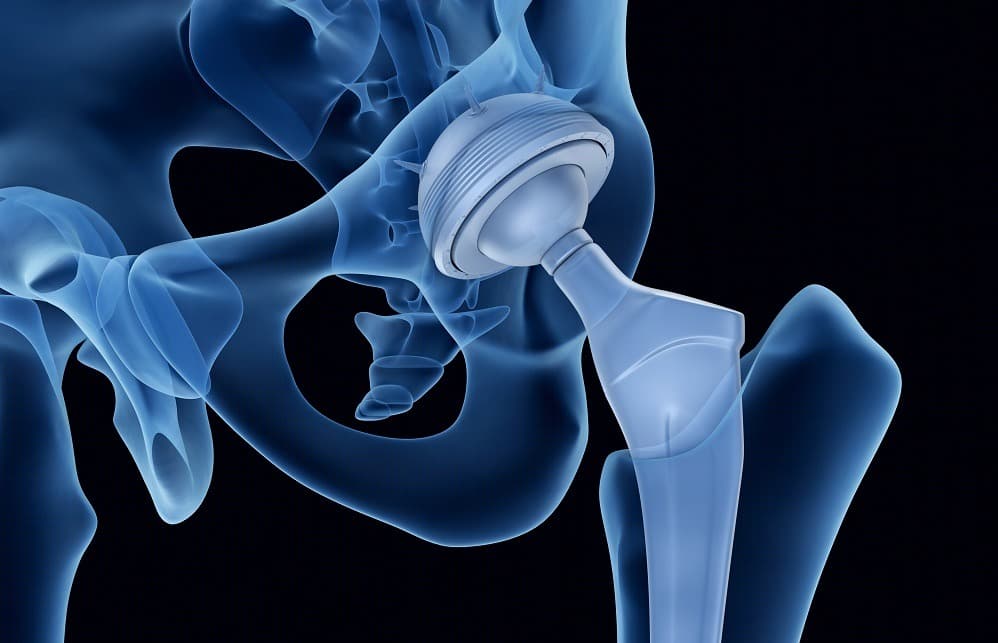

Hip replacement surgery, also known as hip arthroplasty, is a transformative medical procedure aimed at alleviating chronic pain and restoring mobility in patients suffering from severe hip joint damage. This surgery is predominantly performed on individuals affected by osteoarthritis, rheumatoid arthritis, or traumatic injuries that have led to the deterioration of the hip joint. During the procedure, the surgeon removes the damaged cartilage and bone from the hip joint and replaces it with prosthetic components made of metal, ceramic, or high-density plastic. The prosthetic joint is designed to replicate the natural movement of the hip, allowing patients to regain a significant degree of function and mobility.

There are two main types of hip replacement surgery: total hip replacement (THR) and partial hip replacement. In a total hip replacement, both the acetabulum (the hip socket) and the femoral head (the ball of the thigh bone) are replaced. In a partial hip replacement, only the femoral head is replaced. The choice between these procedures depends on the patient's specific condition and the extent of joint damage.

The surgery typically involves making an incision over the hip joint, dislocating the hip to gain access to the damaged area, and then carefully removing the diseased tissue. The prosthetic components are then implanted and secured in place, often using bone cement or a press-fit technique that encourages natural bone growth around the implant. The procedure usually takes a few hours and is performed under general or regional anesthesia.

Total hip replacement (THR), on the other hand, involves replacing both the femoral head and the acetabulum with prosthetic components. This comprehensive approach is often necessary for individuals suffering from severe osteoarthritis, rheumatoid arthritis, or other degenerative conditions that affect both parts of the hip joint. During a total hip replacement, the surgeon removes the damaged cartilage and bone from both the femoral head and the acetabulum, replacing them with artificial components made of metal, ceramic, or plastic. The prosthetic components are designed to mimic the natural movement of the hip joint, providing significant pain relief and improved mobility.

Total hip replacement surgery involves the use of various materials to create prosthetic components that replace the damaged parts of the hip joint. These materials are carefully selected for their durability, biocompatibility, and ability to replicate the natural movement of the hip. The primary components of a total hip replacement include the femoral stem, femoral head, acetabular cup, and a liner that fits within the acetabular cup.